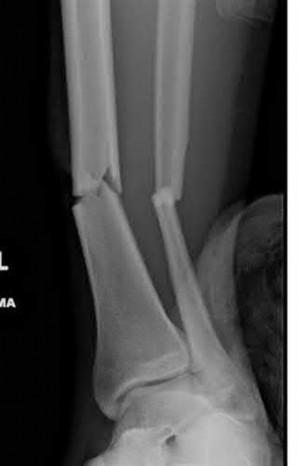

Figures A and B are the Lateral and AP radiographs of a displaced talar neck fracture with tibiotalar dislocation. Figures C and D are the post-reduction sagittal foot CT cuts that reveal a displaced talar neck fracture with medial

comminution.

The patient has sustained a displaced talar neck fracture with medial comminution which requires open reduction and internal fixation to restore anatomic alignment. The patient has likely sustained varus malunion which is a common deformity noted with non-anatomical reduction leading to hindfoot supination and decreased eversion.

Talar neck fractures, while uncommon, can lead to significant morbidity in the ambulatory patient. Treatment of these injuries requires prompt reduction due to the tenuous blood supply to the talus. The most common complications noted after a talar neck fracture are avascular necrosis, subtalar arthritis, tibiotalar arthritis, and varus malunion. A talus varus malunion generally occurs due to medial talar neck comminution and/or non-anatomic reduction of the injury. This deformity can lead to decreased eversion and a supination deformity causing patients to ambulate on the lateral aspect of the foot. These malunions are generally treated with a medial opening wedge osteotomy.